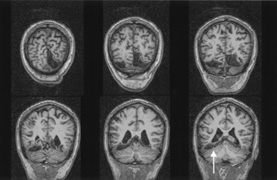

Fig. 15. Bilateral incomplete hemianopia. A 69-year-old man with decreased vision after prostate surgery. A. Fields show remaining central parafoveal vision with some sparing of inferior left quadrant. Note how the defect respects the vertical meridian. B. MRI shows bilateral medial occipital infarction, with sparing of the occipital poles, accounting for the macular-sparing bilaterally. (Courtesy of Dr. Lucia Vaina.)

Bilateral lesions of striate cortex are not rare. Focal midline lesions such as tumors or traumatic injury may affect both striate cortices concurrently, because the right and left striate cortices face each other on the medial occipital surface. The most common cause, however, is posterior circulation ischemia.57 This can affect both striate cortices either simultaneously or sequentially,57 because the right and left posterior cerebral arteries have a common origin from the basilar artery. Twenty-two percent of patients with a unilateral occipital infarction develop bilateral infarction over 3 years.58 Bilateral incomplete hemianopia is distinguished from bilateral optic nerve or ocular disease by the high congruity of the visual fields and step defects along the vertical meridian which indicate the hemifield nature of the visual loss (Fig. 15).57 Such steps are important to seek with a skilled perimetrist, but even so they can be difficult to demonstrate with bilateral hemiscotomata from occipital pole lesions.59 Bilateral quadrantanopias can occur,47,48 often in patients with prosopagnosia and achromatopsia for example, and may mimic the altitudinal defects of optic neuropathy.